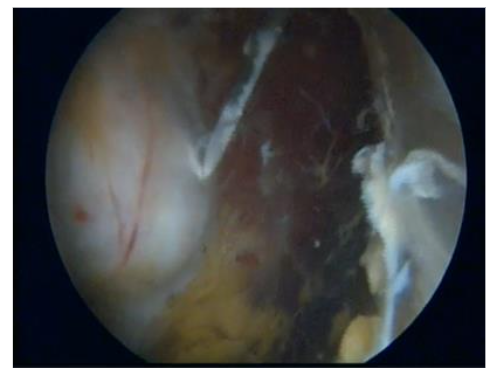

Given that this condition involves tendon insertion (enthesis) in an area with poor blood supply, we utilize the intermediate portal to perform transtendinous perforations in the degenerated tendon regions Figure 5. These perforations are directed towards the greater trochanter to encourage the development of new blood vessels and enhance blood flow, ultimately promoting healing of the lesion, indicating that this method has yielded exceptional results in both clinical evaluations and imaging examinations for partial tears of up to 25% of the total thickness, as illustrated in Figures 6a-b.

Figure 5. Endoscopic greater trochanter perforations